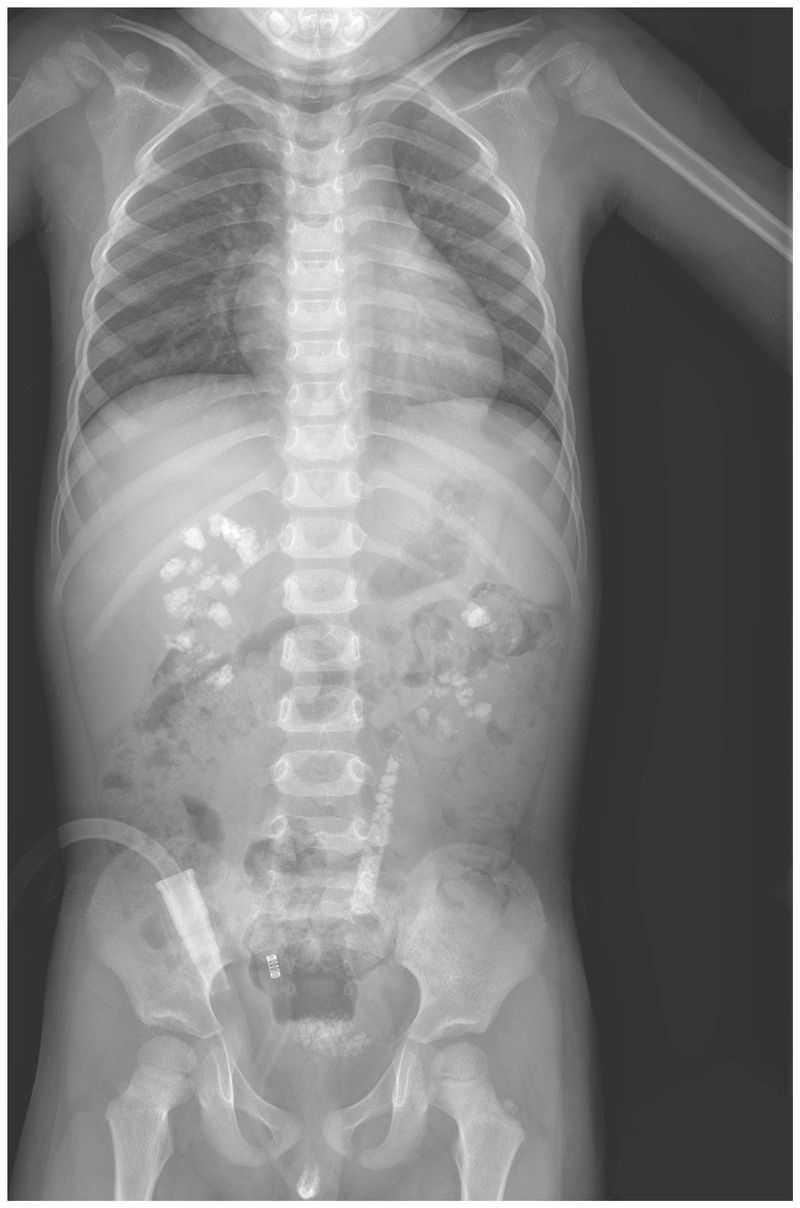

A 3-year-old boy presented to the pediatric urology clinic with a 6-month history of gross hematuria and intermittent abdominal pain. Urinalysis revealed red cells, white cells, and 3+ protein. The serum creatinine level was 0.9 mg per deciliter (80 μmol per liter; normal range in 3-year-old Chinese children, 0.3 to 0.8 mg per deciliter [20 to 70 μmol per liter]). The 24-hour urinary excretion of oxalate was elevated. A radiograph of the abdomen showed stones in the kidneys, bladder, and left ureter. Constituent analysis of the excreted stones indicated that the composition of the stones was more than 95% calcium oxalate monohydrate. On the basis of the clinical data, primary hyperoxaluria type 1 was suspected. Mutational analysis of AGXT, the gene encoding alanine–glyoxylate aminotransferase, confirmed the diagnosis in this patient. Primary hyperoxaluria type 1 is a rare autosomal recessive disorder of glyoxylate metabolism that leads to recurrent urolithiasis alone or in combination with nephrocalcinosis. Supportive measures were initiated, including high fluid intake and oral potassium citrate and vitamin B6. During 1 year of follow-up, the patient continued to have elevated levels of urinary oxalate and multiple kidney stones.